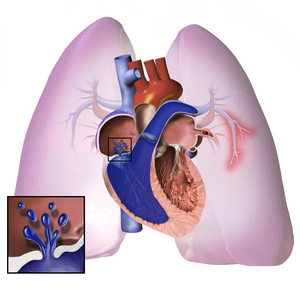

الإصابة

Long standing pulmonary hypertension[16]